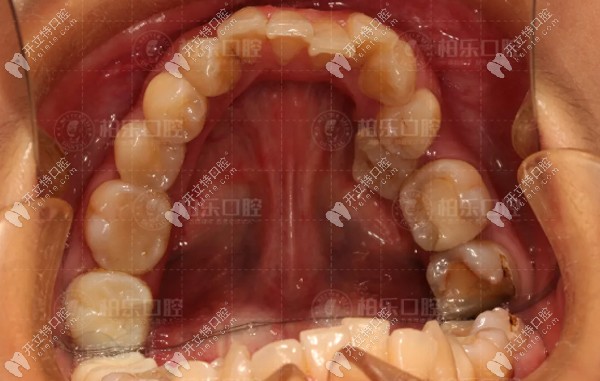

【南寧柏樂口腔門牙反頜矯正前后對比病例】:

南寧柏樂口腔門牙反頜矯正前后對比<span style=

矯正方案:隱形牙齒矯正19個月

矯正醫(yī)生:董瑜

顧客反饋:我在柏樂做了隱形矯正,對于這次的正畸效 果很不錯,總體算下來,就是覺得價格高了些,其它都很滿意。